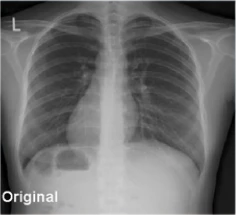

Veja a diferença que nossa tecnologia faz nas imagens médicas

O iRAD aprimora imagens de raio-X revelando características difíceis de ver, melhorando contraste, nitidez e realce de bordas, proporcionando diagnósticos mais precisos com menor exposição à radiação.

Original

Processado com iRAD